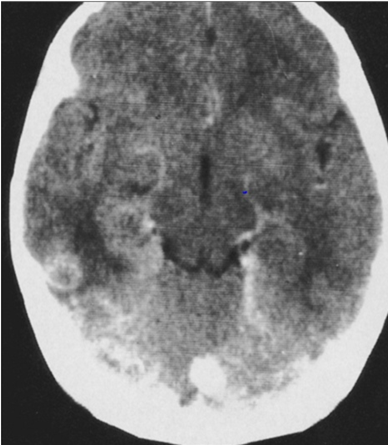

abnormal mri brain Cryptococcosis

• —Cryptococcosis is the most common fungal infection in patients with AIDS

• —. a yeast with a polysaccharide capsule

• —CNS infection is usually secondary to pulmonary infectio

• —nmeningitis, meningoencephalitis, or cryptococcal mass

• —. Meningitis is the most common presentation.

• —Ocular symptoms are common in patients with cryptococcal meningitis.